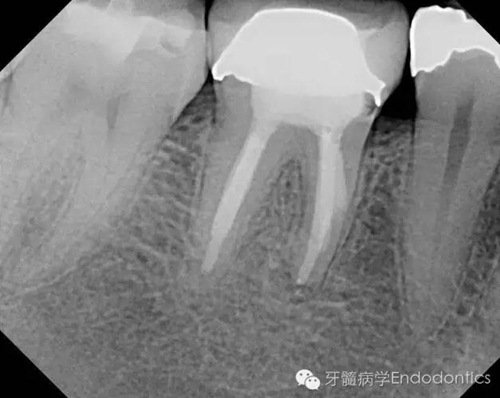

我決定對(duì)患牙行一次性根管再治療。我成功的取出了一根斷針和三根(其中兩根超出根尖)Thermofil(固核載體)。對(duì)所有根管進(jìn)行徹底的清理、成形,干燥后使用熱牙膠垂直加壓技術(shù)完成充填。

兩年后復(fù)診,病變愈合。

圖5.根充后X線片

圖6.隨訪兩年后X線片